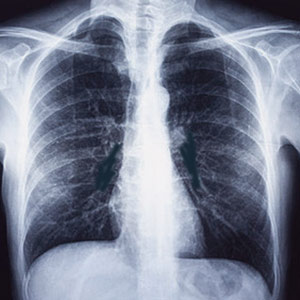

Chest X-Ray

When your cardiologist wants to study the condition of your heart, lungs, blood vessels, airways, and the bones of your chest and spine, he/she will recommend you to go for a chest x-ray. A Chest x-ray is pretty common and often comes among the first few procedures your doctor will recommend if they suspect a heart or lung disease. A Chest x-ray is also used to check how you are responding to a particular treatment. A proper chest x-ray can detect cancer, infection or air collecting in the space around the lung, which might end up in a lung collapse. A Chest x-ray also helps to detect changes in the size and shape of your heart, indicating heart failure, heart valve problems, calcium deposits, fractures, postoperative changes, a pacemaker insertion, and more.